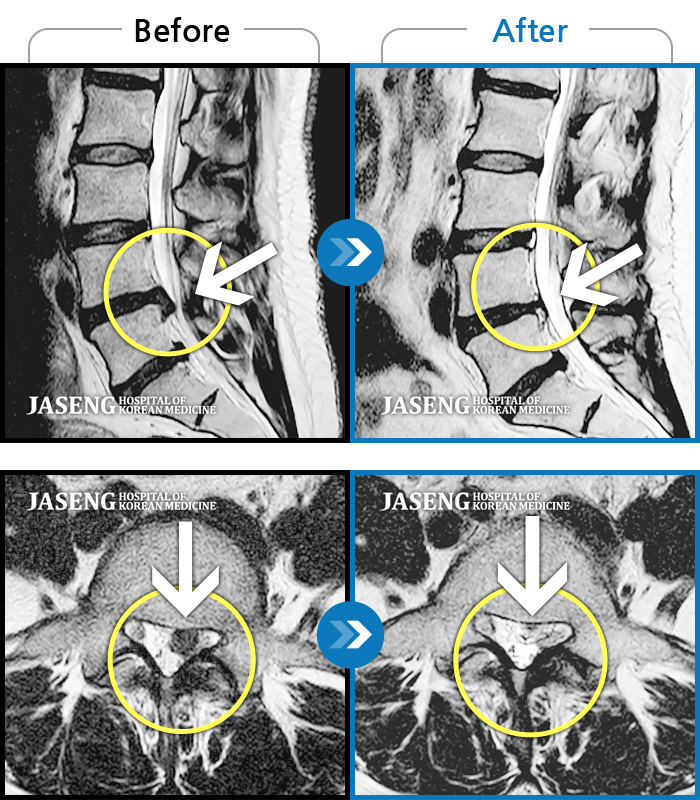

허리디스크

천안 · 김세정 원장

좌측 다리 저림이 매우 심해 야간통증 및 일상 생활에 제한이 많은 상태로 내원하였습니다.

촬영시기

2021.08.07 ~ 2024.07.22